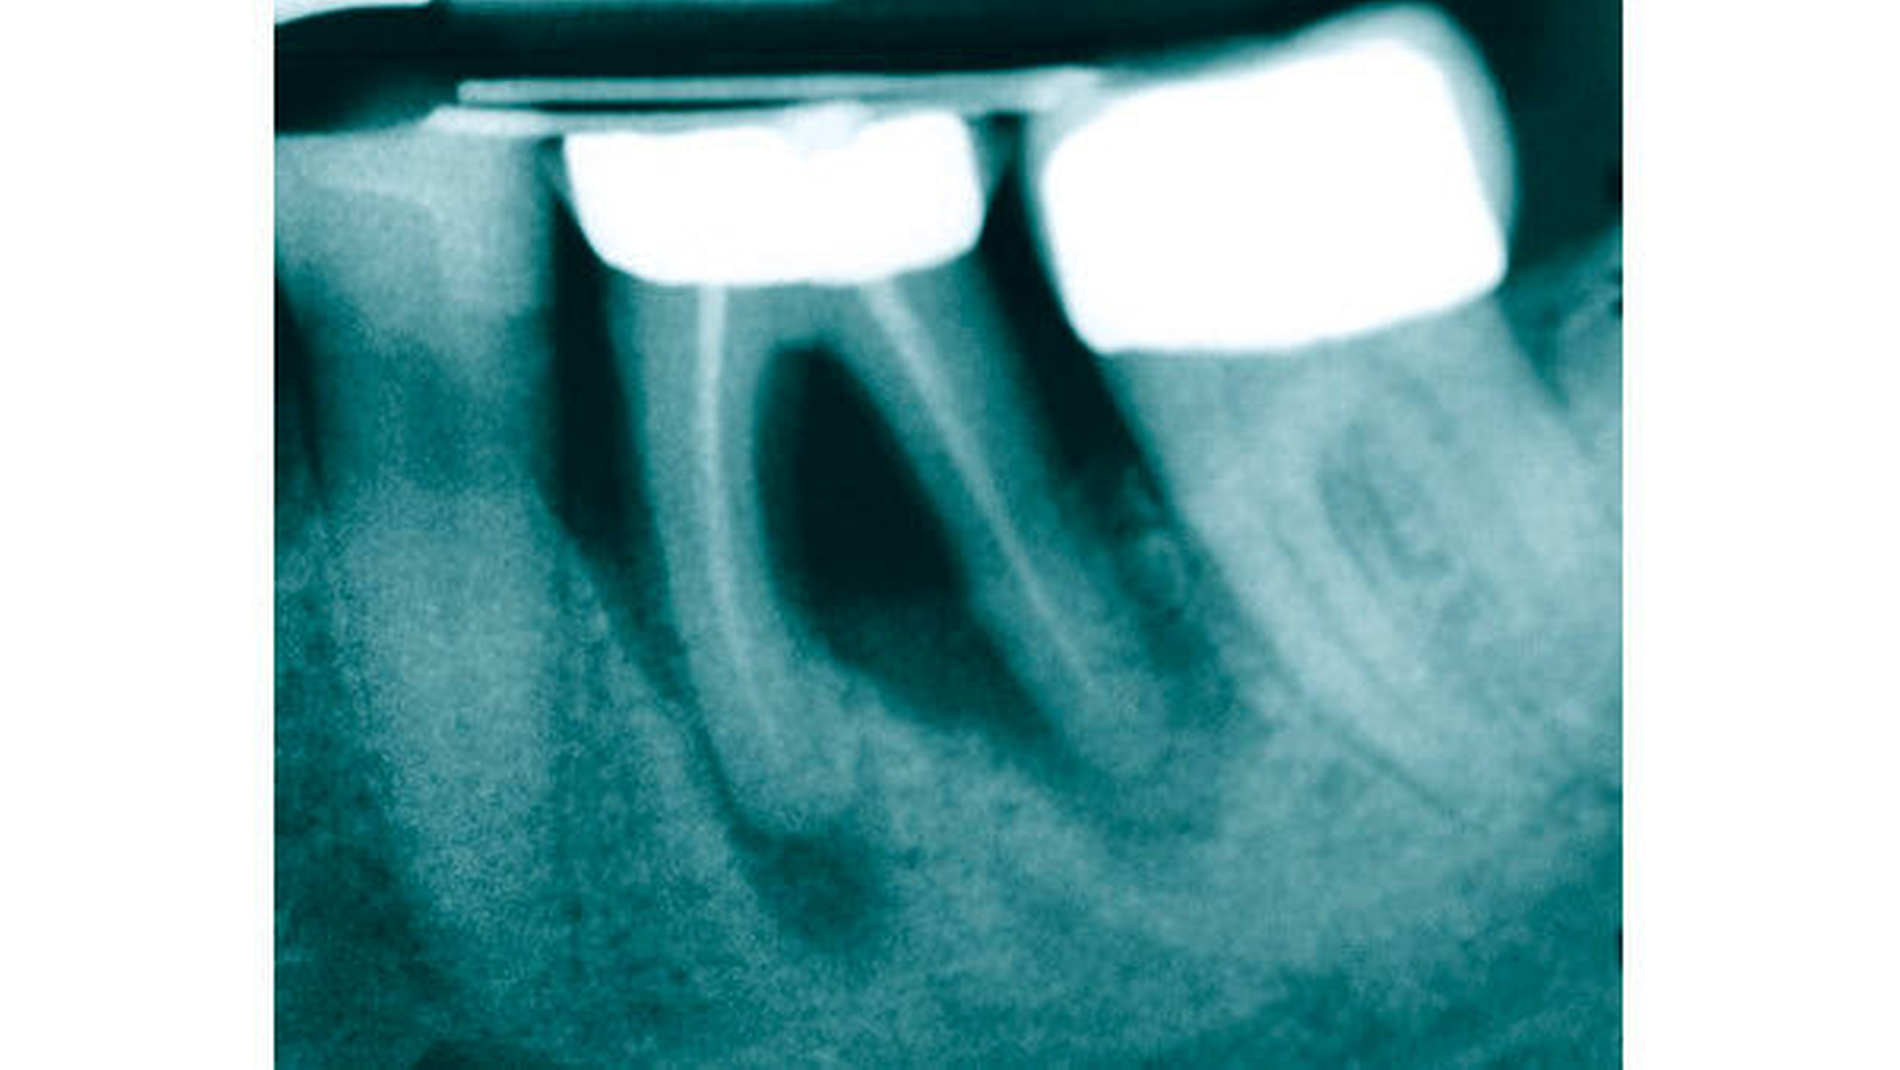

Bei Zahn 36 zeigte sich zu Beginn der Behandlung eine massive Osteolyse (Abbildung 8). Die anfängliche Diagnose lautete: massiv vorangeschrittene Paro-Endo-Läsion mit Osteolyse von rund 80 Prozent mit Furkations- und Lockerungsgrad von jeweils III und mit Pusaustritt aus einer vestibulären Fistel. Daher war die Prognose: nicht erhaltungswürdiger Zahn.

Um eine spätere, aufwendige Augmentation zu vermeiden und über einen längeren Zeitraum knochenregenerativ wirken zu können, sollte Zahn 36 vor der späteren Extraktion forciert aus der Alveole bewegt werden. Die insuffiziente Wurzelbehandlung spielte zu diesem Zeitpunkt aufgrund der infausten Prognose keine Rolle.

Nach forcierter Extrusion (Abbildung 9) mit vier Gummiwechseln innerhalb von acht Tagen und einer ersten Stabilisierungsphase zeigten sich im Röntgenbild (Abbildung 10) erste, deutliche Reossifkationen.